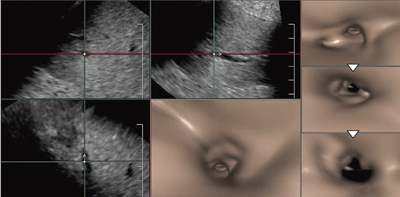

次に,3D画像であるFly Thruの肝がん診断への応用について述べる。

東芝メディカルシステムズの超音波診断装置のメカニカル4Dプローブには,腹部用のコンベックスとマイクロコンベックス,乳腺,甲状腺,体表用のリニアをメカニカルに振るもの,経直腸,経膣用があるが,これらすべてでFly Thruが可能である(図7)。Fly Thruは,シングルスイープでボリュームデータを取得し,そのボリュームデータから"High Density Rendering"という高速画像取得・演算を行う。簡単で高速なボリューム操作を実現する新しいエンジンで画像処理を行うことで,高画質のデータを最大限に生かした透視投影像を再構成する。

Fly Thruによる肝への応用で高いポテンシャルが期待されるのは,肝内門脈の病変である三次分枝の門脈腫瘍栓(VP1)の診断である。肝細胞がんにおいて,門脈の末梢に浸潤するVP1は,従来の画像診断では診断が不可能で,外科切除標本の病理検査が必要だった。例えば,肝細胞がんでは,超音波画像で病変に隣接して門脈枝や肝静脈枝が走行している場合,通常の超音波断層像では,門脈内にVP1があるかどうかは診断できない。高画質のBモード画像でも,血管が細く蛇行しているため,診断は困難である(図8)。造影超音波でも,血流があり閉塞していないことは確認できるが,VP1かどうかの診断には至らない。

しかし,造影なしのファンダメンタルBモードによる3Dのボリュームデータから再構成したFly Thruでは,細い門脈枝の中心を自動的に移動して観察することで,腫瘍の近傍で隆起はあるが閉塞はしていないことが確認できる(図9)。肝内の脈管に関してFly Thruに期待するのは,内膜側の変化を見ることではなく,管腔内を自動で移動して内膜が変化している場所を特定し,その部分の断層面を観察することである。Fly Thruの元になる情報は断層像であり,直接の浸潤を受けていなければ,脈管と腫瘍との間には一定の距離があることが考えられる。脈管内の変化から疑わしい場所を特定して,その部位で仮想の“メス"を使って断層を自由に切って観察することで,浸潤の有無を診断することが可能ではないかと考えている。

図9 肝内門脈枝のFly Thru画像

腫瘍近傍を走行する門脈枝の中に腫瘍栓がないことがわかる。